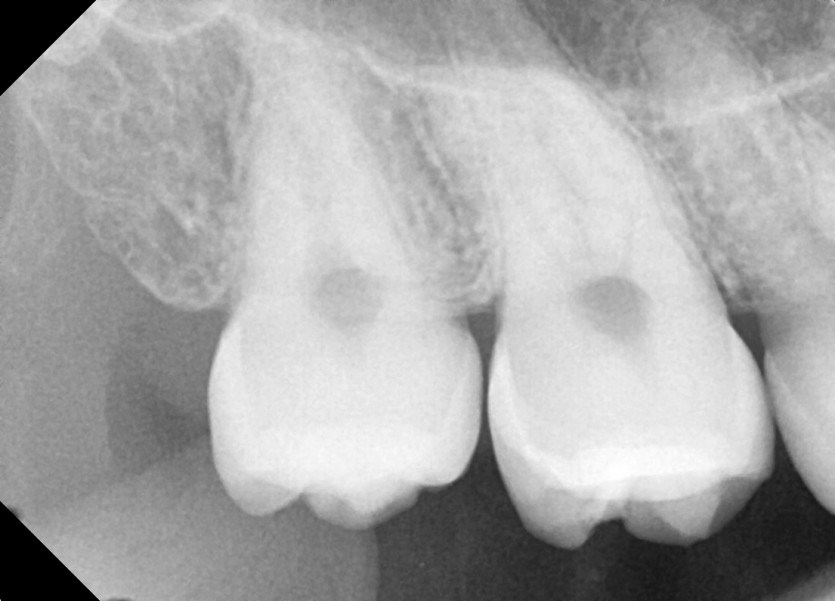

#18,48 사랑니 발치

구강외과 전문의가 당일발치했습니다.